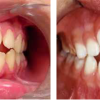

Ancyloglossia

Kaasasündinud anomaalia, mille juures keel on tugevalt fikseerunud suupõhjas. Selline anomaalia oluliselt ei takista rääkimist, kuid takistab loomulikku suuõõne (hambad, suuesik) puhastumist keele abil ja foneetikat. Keelekida haavandumine tekib pideva...